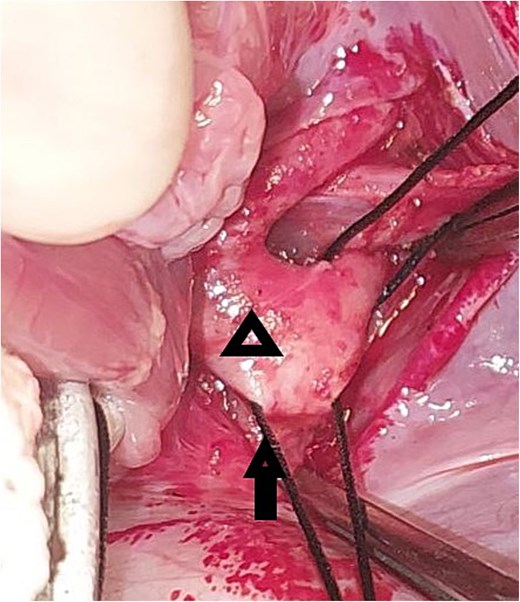

A 20-day-old boy with an unremarkable perinatal history was referred to the pediatric emergency department with respiratory distress. The physical examination revealed poor general condition and central cyanosis. The pulses were bounding in both brachial arteries but the femoral arteries were not palpable. A systolic murmur grade 4/6 was heard along the left sternal edge. The liver was enlarged 2 cm below the costal margin. Transthoracic echocardiography (TTE) was performed and revealed infracardiac TAPVC with associated CoA. Computed tomography angiography (CTA) confirmed the diagnosis of CoA (Fig. 1), and for technical issues, the pathway of CPC was not apparent on CTA. TTE was repeated and the drainage of the CPC into the portal vein was confirmed. The heart team at our hospital decided for urgent surgical repair. At first, the repair of CoA was performed through left thoracotomy with patch plasty technique since the stenosis was too long, and it was not possible to perform resection and end-to-end anastomosis. Then, through median sternotomy, the pericardium was opened, and a total cardiopulmonary bypass (CPB) was prepared. The heart was arrested with an antegrade cold blood cardioplegic solution. The CPC was seen behind the pericardium (Fig. 2). The VV was descending crossing the diaphragm, and it was dissected and controlled (Fig. 3). The heart was lifted out of the pericardium and a long incision was made in LA, and a parallel incision was made in the CPC (Fig. 4). A wide anastomosis was performed between these two incisions thus connecting the CPC into LA. The VV was permanently closed. RA was opened, and a small ASD was closed. The remainder of the operation was completed uneventfully. The patient was weaned off the CPB with stable hemodynamic conditions on low-dose inotropes (milrinone, epinephrin). Postoperative TTE showed normal pulmonary venous drainage without any gradient across the anastomosis, and excellent repair of CoA. After 48 hours on mechanical ventilation, the patient was extubated, and discharged from the ICU after 5 days. On one year follow-up, the patient was with normal growth, and in very good general condition without any complaints. TTE during the follow-up period revealed normal flow in the pulmonary veins.

Intraoperative image showing the opened left atrium (the arrow), and the opened pulmonary confluence (the star).